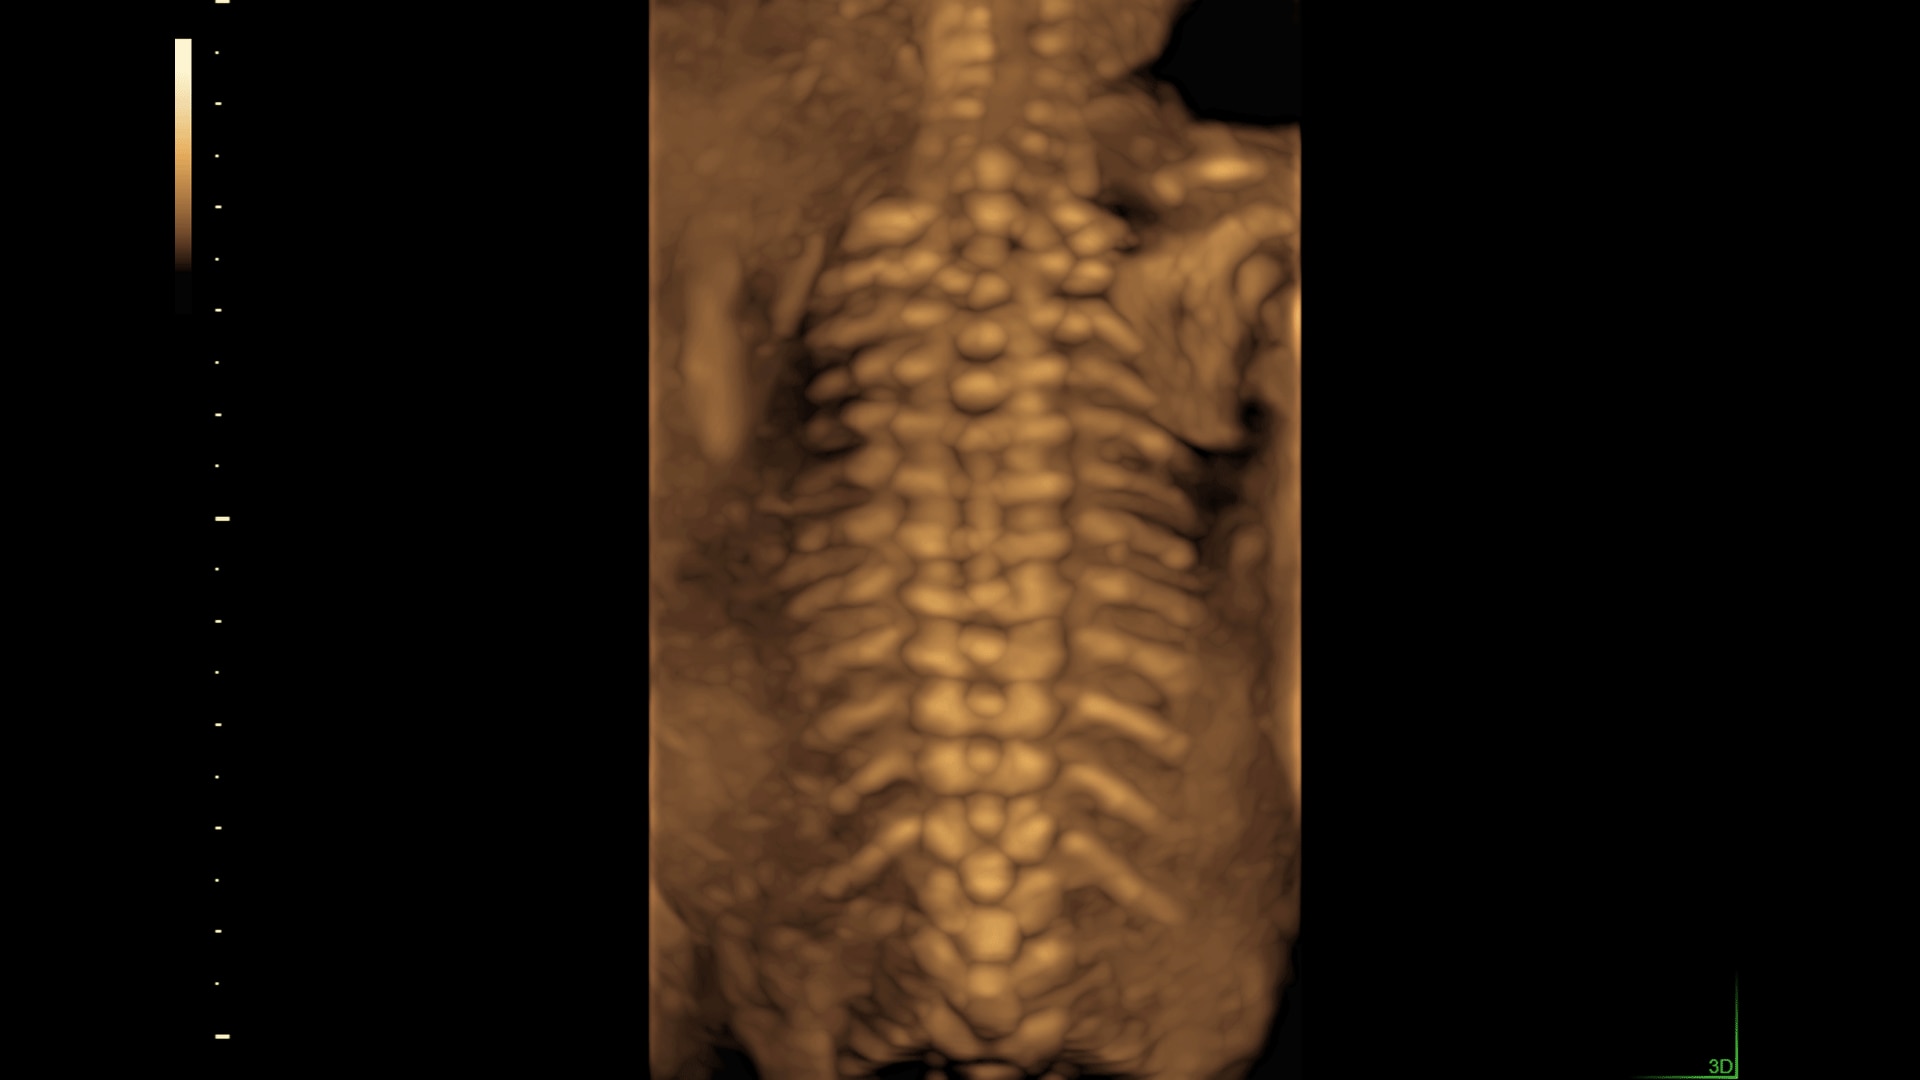

SonoCNS

Simplify assessment of the fetal brain with SonoCNS. This sophisticated, AI-powered, deep-learning technology helps properly align and display recommended views and measurements of the fetal brain.